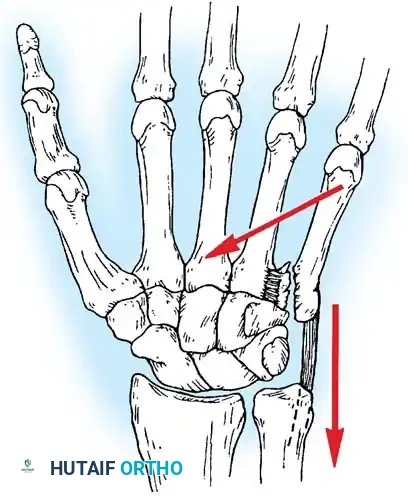

Biomechanics of the "Reverse Bennett" Fracture

Bora and Didizian highlighted the potentially disabling nature of intraarticular fractures at the base of the fifth metacarpal. This joint is highly mobile, permitting approximately 30 degrees of normal flexion and extension, alongside the crucial rotation necessary for power grasp and palmar cupping.

The pathoanatomy is directly analogous to a Bennett fracture of the thumb. The extensor carpi ulnaris (ECU) tendon inserts robustly onto the dorsal base of the fifth metacarpal. When an intraarticular fracture separates the base, the unopposed pull of the ECU displaces the metacarpal shaft proximally and dorsally, while the small articular fragment remains tethered to the hamate by the strong volar ligaments.

Failure to anatomically reduce a fifth metacarpal base fracture results in a malunion that severely compromises the 30 degrees of essential CMC mobility, leading to profound weakness of grip and chronic, painful arthrosis.

Standard AP and lateral views are insufficient for a complete evaluation. A specialized radiograph taken with the hand in 30 degrees of pronation is required to profile the fifth CMC joint and accurately assess the articular surface and the degree of proximal migration.